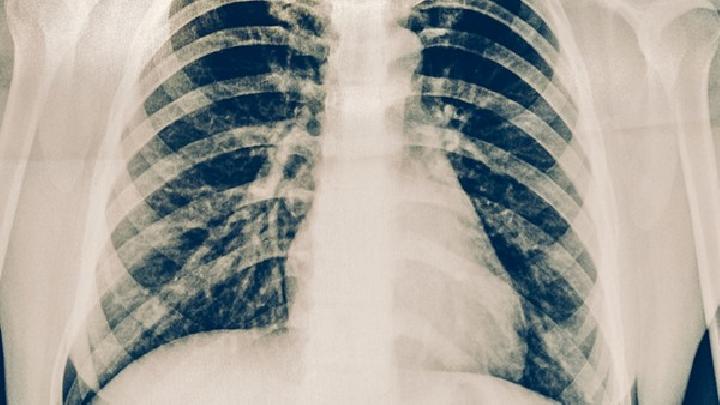

怎样发现早期肺癌

肺癌是大家很熟悉的一个疾病,可以说是“谈癌色变”,罹患肺癌是非常痛苦的事情,危及人的生命,近年来国内的肺癌发病率也越来越高,死亡率居高不下。大家对肺癌的早期症状不怎么了解,也想知道肺癌的前兆都有什么,现在小编来给大家普及一下。

肺癌的前兆与早期症状大致相似,在全身可表现为:消瘦、发热、贫血。在局部可以表现为:胸痛、气急、胸闷、咳嗽、声音嘶哑等。